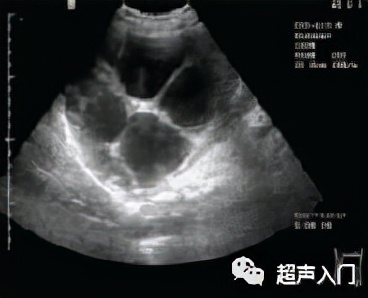

2、多囊型

表现为大的囊肿内有多个大小不等圆形小囊,呈葡萄状或蜂窝状,形成特征性 “囊中囊”征象。

多子囊型(CE2)

图源:人卫出版社教材及课件